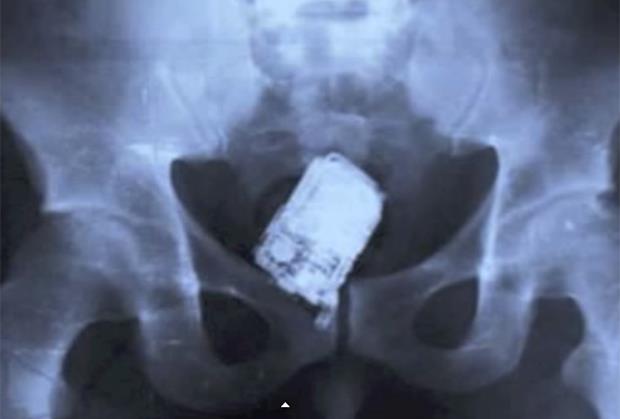

LUDOSTI: 25 najčudnijih stvari koje je rendgen snimio u ljudskom telu